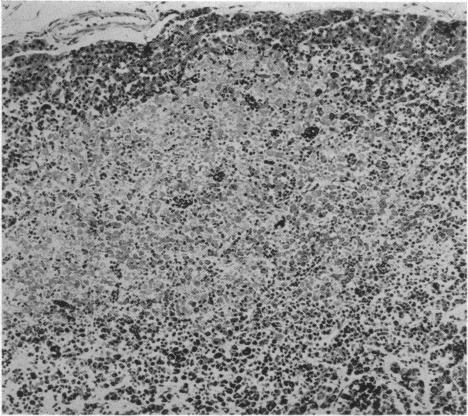

Leukaemia and diabetes insipidus; case report, with unexpected effect of cortisone.

Br Med J. 1956 Jun 9;1(4979):1328-31. doi: 10.1136/bmj.1.4979.1328.